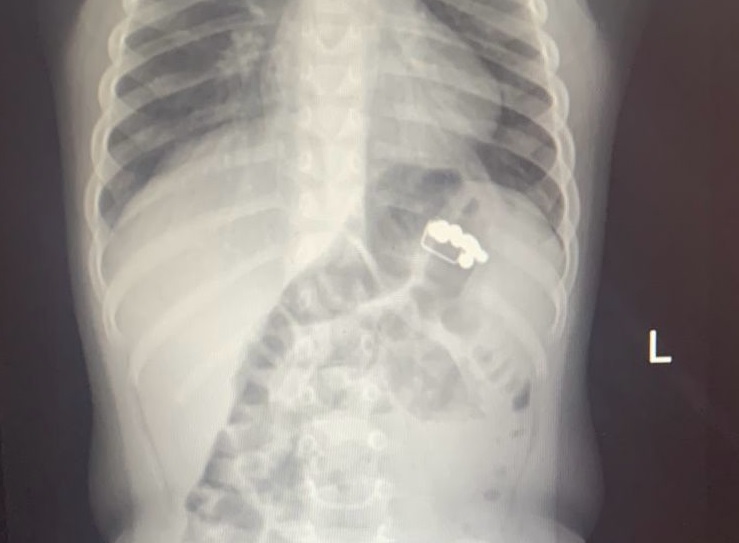

Ребенок съел пакетик